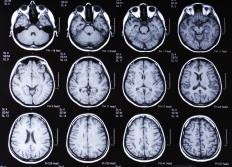

大脑 MRI 扫描。一些 MRI 扫描仪使用相同的功能一组用于超导磁体的带电线圈和电线,但没有液氦来保持冷却。以这种方式使用,线圈和电线会产生电阻磁体,而不是超导磁体。如果没有液氦的冷却作用,超导性就无法实现;相反,使用更强大的电流来产生稍弱但仍然有效的磁场。另一种可用于 MRI 扫描的初级磁体是永磁体。永磁体实际上是巨大的磁铁,不断地发出磁力ff 磁场。由于其尺寸和重量,它们不是 MRI 机器中最受欢迎的磁铁类型。

脑部 MRI 对研究人员和医生都很重要。MRI 机器能够提供详细的信息法师身体任何地方的软组织。这使得它们成为检测脑出血、乳腺癌和韧带损伤等软组织疾病的理想选择。 MRI 机器的另一个优点是它们不会发出任何辐射。虽然 X 射线等扫描方法产生的辐射尚未被证明有害,但患者知道自己不会暴露于任何辐射下,这通常能让患者安心一些。